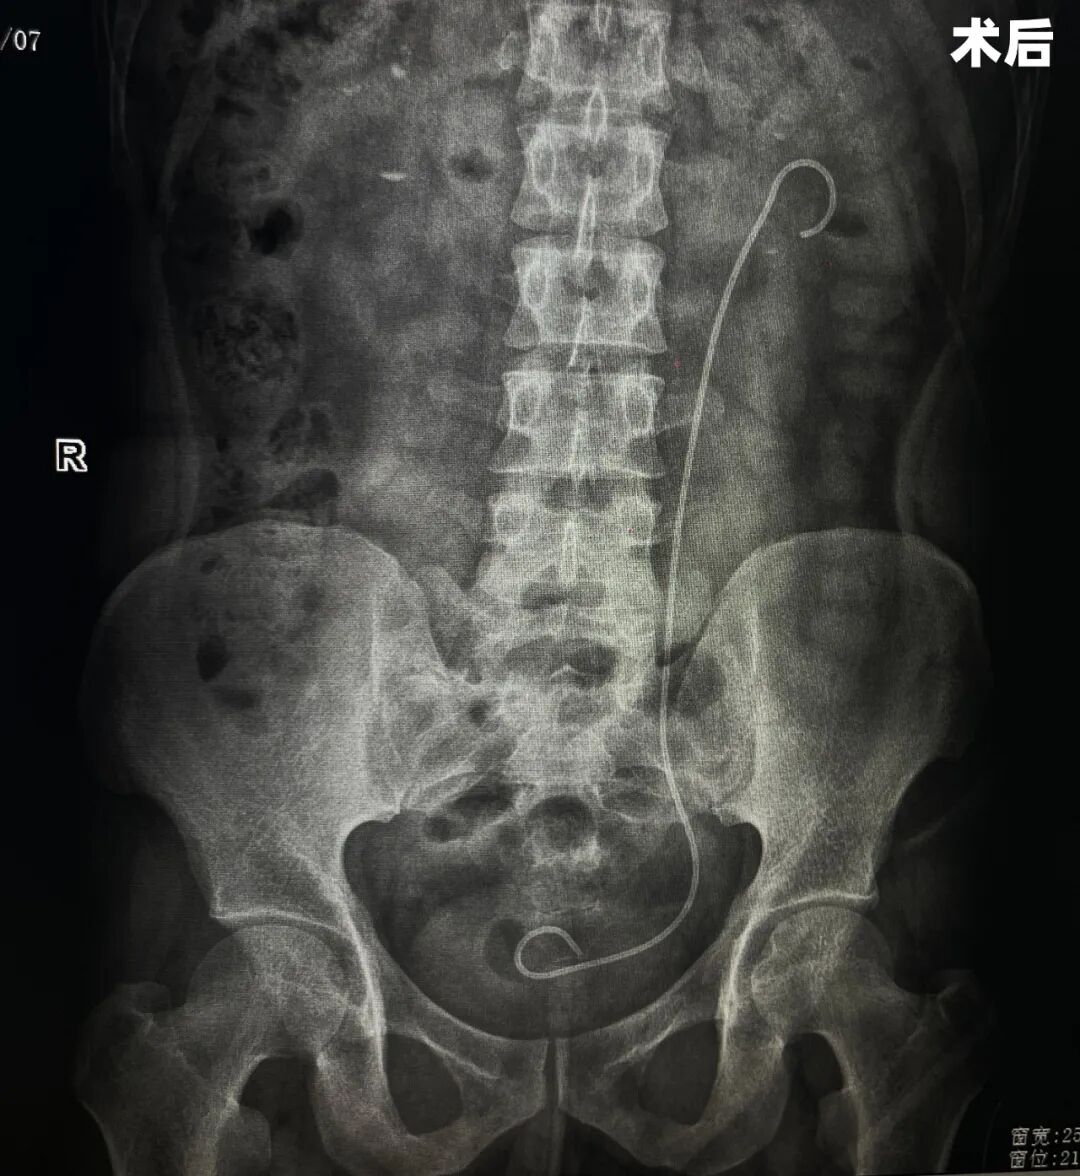

术后

在与患者及家属充分沟通后,手术团队制定了科学严谨的手术方案,拟行经皮肾镜下左肾结石碎石取石术,并同步实施输尿管支架置入术及经尿道膀胱镜下左侧输尿管导管插入术,以确保引流通道通畅、降低术后感染及梗阻风险。

图片

术中,团队凭借积累多年的技术与默契的配合,精准建立经皮肾穿刺通道,利用肾镜清晰显示结石位置,通过碎石系统将结石逐步击碎并清除。手术过程顺利,术中出血量少,未出现并发症。针对患者乙型病毒性肝炎的特殊情况,麻醉科及手术室护理团队在术中严格执行感染控制流程,确保手术环境安全。